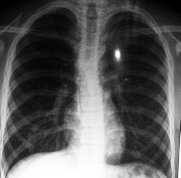

Luego de la evacuación, reinició DP automatizada con volumen bajo de infusión (20 ml /Kg.) disminuyendo el tiempo de permanencia y ubicando al paciente en posición semisentada. A pesar de las medidas adoptadas reapareció el derrame y persistió la dificultad en el drenaje. Debido a la recidiva del derrame, se transfirió al paciente a hemodiálisis. (Figura 3)

Figura 3. Control radiológico un mes más tarde con desaparición completa del derrame